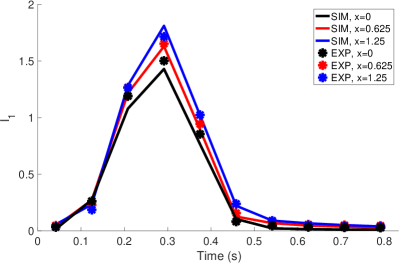

Pressure and flow waveforms from the second cycle in the simulation and the experiment are shown in Figure 7. During systole, the pressures were prescribed. During valve closure, the pressures showed an oscillation as determined by the interaction of the prescribed pressure and resistance (Equation 14). The experimental pulmonary artery pressure had a similar oscillation, but not with precisely the same magnitude or frequency. The RV flow rate closely matched that of the experimental flow. The RPA flow was somewhat greater than the experimental RPA flow, and the LPA flow was somewhat less than the experimental LPA flow. The total experimental flow was not precisely conserved, which is expected given pointwise uncertainty in the 4D flow MRI velocity measurements of 4.7 cm/s, uncertainty in gating of the cardiac cycles and variation from cycle to cycle. The total experimental inflow minus total outflow was up to 27.0 ml/s, which is nearly all experimental uncertainty, as the vessel maintains approximately constant volume. Therefore, it was not possible to simultaneously match all three experimental flow rates. All three simulation flow rates showed a substantial oscillation at the beginning of diastole. Similar oscillations in the experimental flow rates almost surely occurred but could not be captured due to the time resolution of the 4D flow MRI data. We estimated the stroke volume to be 46.11 ml and cardiac output to be 3.32 L/min. Using the maximum flow rate of ml/s and diameter of the valve, 2 cm, as the length scale, we estimated the peak Reynolds number of the flow as

The integral metric indicated that the streamwise momentum of the jets in both simulation and experiment are very similar. The value of over the cardiac cycle is also shown in Figure 9 on the three slices 0, 0.625 and 1.25 cm. Values remained close between simulation and experiment throughout systole and diastole. In both simulation and experiment, the value of increases monotonically from the annulus slice at cm to the most distal slice at cm.